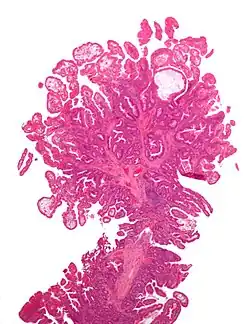

| Type | Risk of containing malignant cells | Histopathology | Image | |

| Hyperplastic polyp | 0% | No dysplasia.[10]

|

| |

Hyperplastic polyp

Most hyperplastic polyps are found in the distal colon and rectum.[18] They have no malignant potential,[18] which means that they are no more likely than normal tissue to eventually become a cancer.

Microvesicular hyperplastic polyp. H&E stain. -